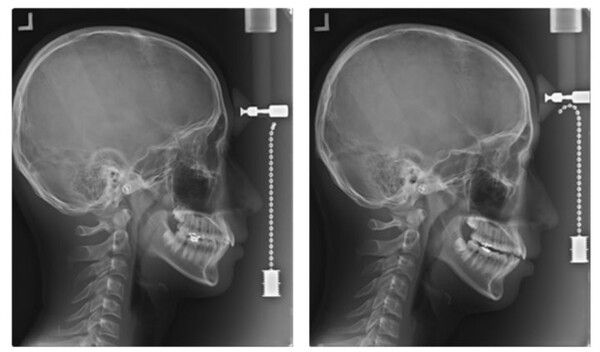

최근 안전은 물론 효능·효과가 검증되지 않은 '셀프 치아장치' 사용으로 인해 오히려 구강 건강을 해치는 사례가 발생하고 있어 각별한 주의가 요구되고 있다.

뉴시스 보도에 따르면, 2일 대한치과의사협회에 따르면 일부 온라인 쇼핑몰에서는 치과의사의 진단 없이 환자 스스로 이갈이나 코골이 방지 또는 치아교정이 가능한 것처럼 홍보하며 마우스피스를 판매하고 있다.

하지만 이러한 ‘셀프 치아장치’는 효과도 담보할 수 없을 뿐 아니라 예기치 못한 심각한 부작용들을 유발하는 것으로 파악됐다.

실제 구입한 '셀프 치아장치'로 인해 ▲치아나 잇몸의 손상 ▲부정교합 ▲턱관절 장애 유발 ▲파손 또는 파절로 인한 기도흡입 등 다양한 부작용 유발 사례들을 찾아볼 수 있다.

대한치과교정학회는 "비전문가에 의한 셀프 교정장치는 치아 파절, 치아 괴사, 치관 파절, 치근 파절, 치아발거, 잇몸 및 연조직의 외상과 궤양, 치조골의 상실, 보철물의 탈락 등 다양한 부작용이 발생할 수 있는 것으로 보고된 바 있다"며 "전문가인 치과의사에 의한 진단 및 치료계획의 부재와 더불어, 교정 진행과정에서 유발되는 관찰과 치료계획의 변경도 불가해 소비자의 피해를 최소화할 수 있는 최후의 기회마저 박탈될 수 있다"라고 밝혔다.